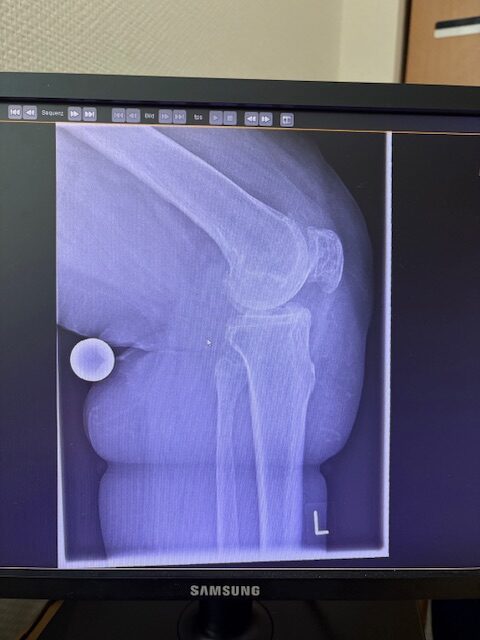

Η 80χρονη ασθενής παρουσίαζε έντονο πόνο και δυσκαμψία στο αριστερό γόνατο τα τελευταία χρόνια. Ο πόνος είχε επιδεινωθεί, επηρεάζοντας τη βάδιση και τη συνολική κινητικότητα, ενώ δυσκολευόταν ακόμα και σε απλές δραστηριότητες όπως το ανέβασμα σκαλοπατιών ή το περπάτημα σε μικρές αποστάσεις. Με την υπάρχουσα πρόθεση ισχίου στην αριστερή πλευρά η ασθενής ήταν αρκετά ευχαριστημένη. Ο ακτινολογικός και κλινικός έλεγχος ανέδειξε προχωρημένη οστεοαρθρίτιδα του αριστερού γόνατος, με πλήρη απώλεια του αρθρικού χόνδρου και παραμόρφωση του μηροκνημιαίου άξονα. Μετά από ανάλυση όλων των επιλογών, αποφασίστηκε η Ολική Αρθροπλαστική Γόνατος με Ρομποτική Υποβοήθηση, με στόχο την απόλυτη ακρίβεια στην τοποθέτηση των εμφυτευμάτων και την αποκατάσταση της φυσιολογικής μηχανικής του γόνατος.

Ο προεγχειρητικός ψηφιακός σχεδιασμός

Πραγματοποιήθηκε σε ειδική ακτινογραφία ολόκληρων των δύο κάτω άκρων. Σε αυτό το ψηφιακό μοντέλο σχεδιάστηκε με ακρίβεια το είδος, το μέγεθος και η ακριβής θέση των προθέσεων, με βάση τα ανατομικά χαρακτηριστικά της ασθενούς.